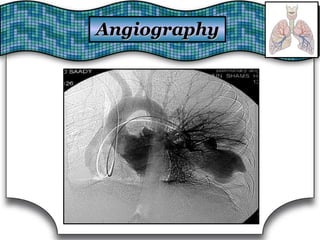

AngiographyAngiography

AdvantagesAdvantages::

1.1. Gold standard diagnostic tool for suspected PE.Gold standard diagnostic tool for suspected PE.

2.2. Diagnosis of arteriovenous malformation.Diagnosis of arteriovenous malformation.

3.3. Allows management of some cases of hemoptysis usingAllows management of some cases of hemoptysis using

endovascular embolization.endovascular embolization.

Disadvantages:Disadvantages:

1.1. Embolization of Spinal arteriesEmbolization of Spinal arteries →→ paraplegia.paraplegia.

2.2. Needs special skills.Needs special skills.